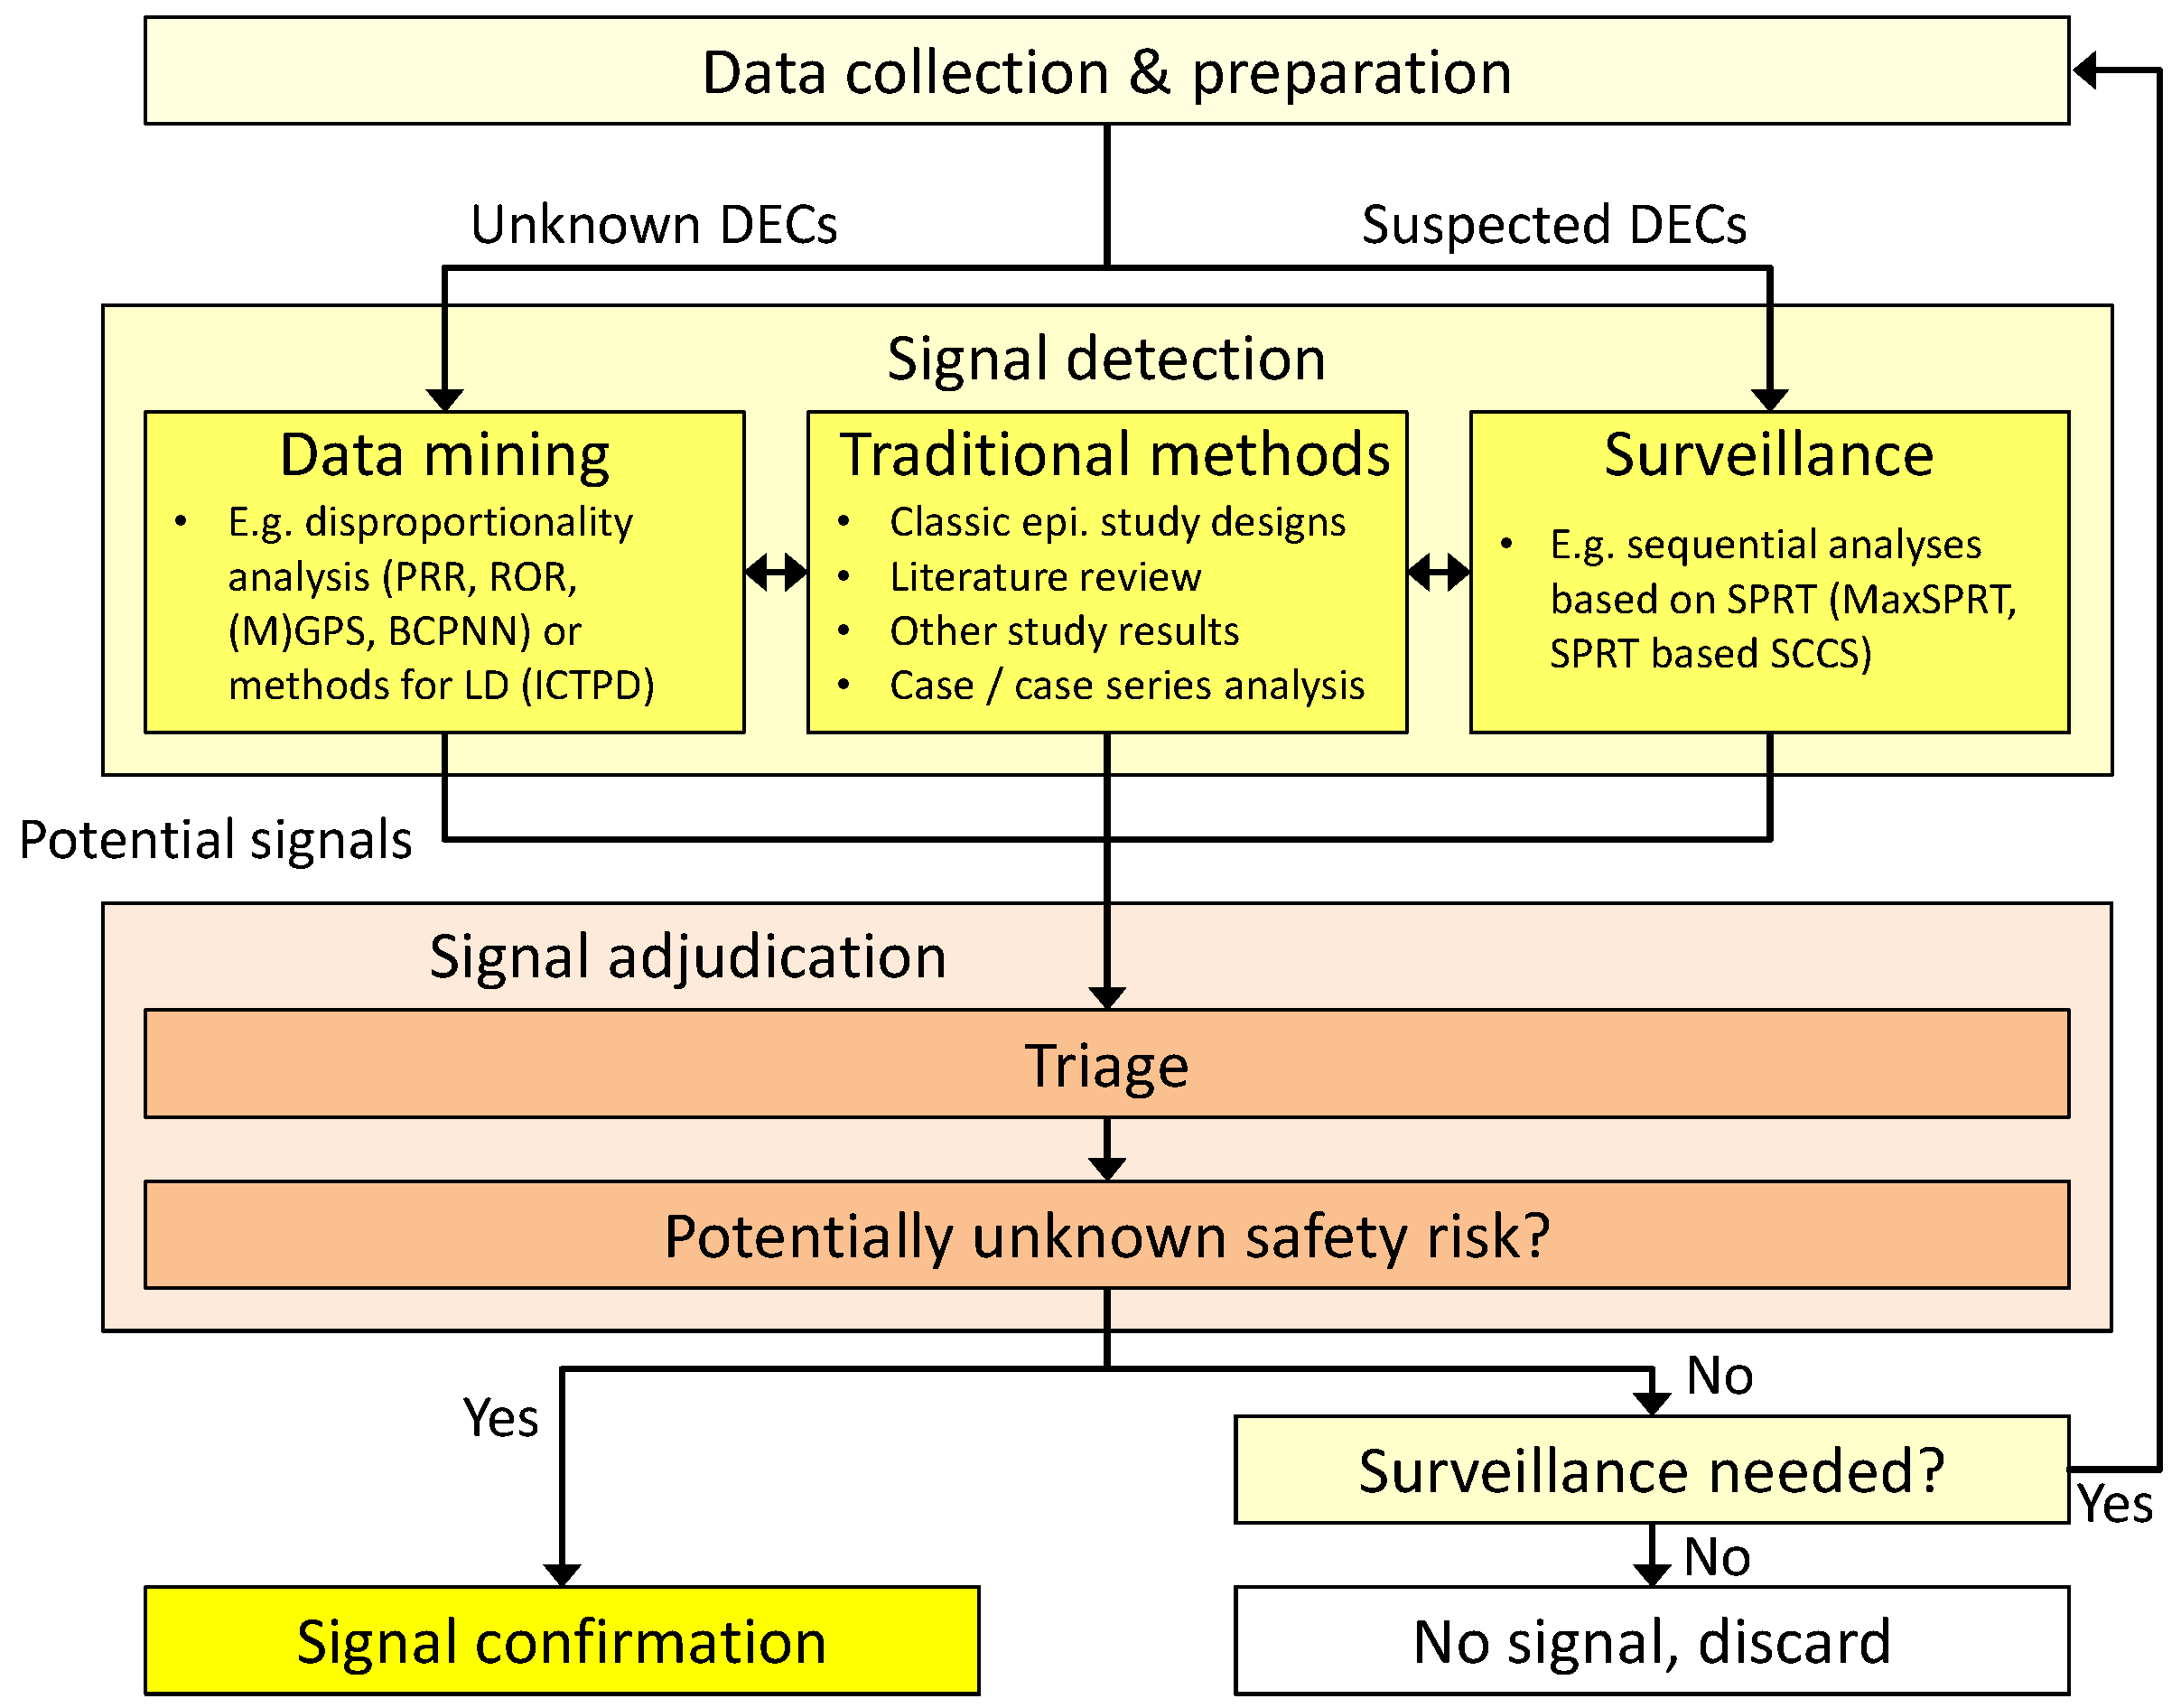

2. General Workflow

- (1)

- Data-mining techniques that strive to uncover so far unknown and unsupected associations. These methods are usually applied to a broad range of combinations of drug exposures and subsequent adverse events, often without limiting the search to pre-defined drug classes or specific medical conditions. They can be regarded as a broad search over the whole spectrum of drug-event combinations (DECs) in the underlying dataset.

- (2)

- If the data-mining search has indicated a possible health risk with a certain DEC, it may be advised to closely monitor this DEC over time to decide whether it should be considered further in confirmatory studies. Surveillance techniques have been developed to consolidate knowledge on these already suspected DECs and are often applied after the first data-mining step.

6. Triage—Adjudication of Potential Signals